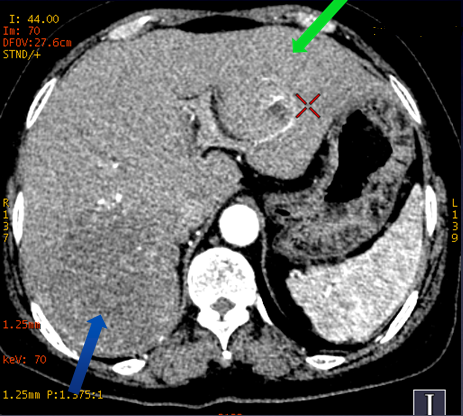

动脉期肝右叶大小相邻两个病灶,大病灶可见早期边缘强化

轴位图像观察到的左右叶病变